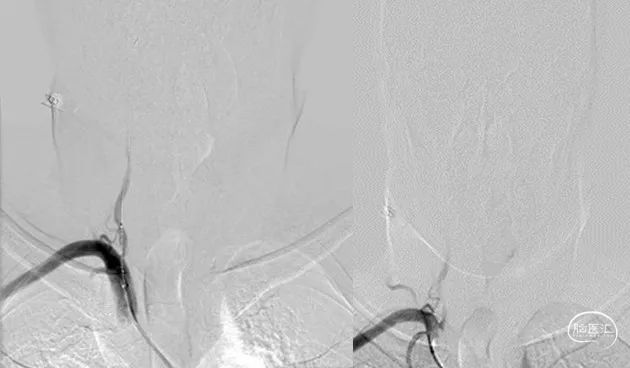

DSA提示:双侧颈内动脉及颅内血管未见明显狭窄,右侧椎动脉优势,左侧椎动脉纤细,V4段闭塞。右侧椎动脉起始处重度狭窄,右椎V4段及基底动脉近端局限性重度狭窄。患者反复间断发作头晕,考虑后循环缺血引起的TIA发作,且强化药物治疗效果不佳,有介入治疗适应症。

左右滑动查看更多

6F导引导管建立通路,先行右侧椎动脉起始处球囊扩张,上行导引导管至V2后,引入球囊导管先后扩张基底动脉及椎动脉狭窄处,再在两处病变进行支架成形术。若起始处扩张残留狭窄程度重,最后行起始处球扩式支架置入。

全麻后,股动脉置入6F血管鞘,6F导引导管配合超滑导丝至右侧锁骨下动脉建立通路,Synchro-14(200cm)微导丝配合4mm×30mm快交球囊定位V1狭窄扩张。

最后保留微导丝在椎动脉内,将导引导管退至锁骨下动脉后,送入5mm×19mm球扩式支架并释放。